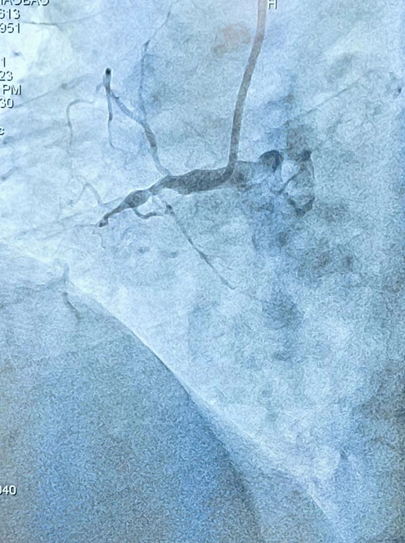

5 月 23 日心血管病医院接诊一位古稀老人,多年的胸闷、胸痛一直困扰着他。反复发作的症状严重影响其正常生活。医院李逢春主任看到病人后,考虑立即给予冠脉造影检查。杨征团队医生熟练完成造影后,发现这位老人的右冠已出现「海蜇头样」慢性完全闭塞性。根据 J-CTO 评分为 3 分,属于难度极高的手术。本着生命至上原则,为改善患者长期预后,杨征手术团队立即开启了一场漫长征程,也是本院首例 CART 技术开通 CTO 病变血管。CART 全称为反向控制性正向和逆向内膜下寻径技术,是目前应用于逆向开通 CTO 病变发展迅速、应用广泛的术式之一。

术前李逢春主任与杨征医生团队仔细阅片,综合评估患者术中经判读冠脉造影提示右冠 1 段完全闭塞,远端可见桥血管及 LCX 提供侧枝逆灌。患者血管自身条件非常差,存在多支病变;CTO 段逆向供血血管环境极差,全程弥漫性病变、严重狭窄伴溃疡。正向逆向均无明显入路,这给术者带来了极大的挑战。

杨征团队尝试正向进入闭塞段,但因其病变部位复杂,导丝触觉反馈提示 CTO 帽钙化严重,立即果断改用逆向开通。但又出现了一个致命性问题,经过冠脉造影发现:因其侧枝循环的特殊性,与回旋支连接,未与间隔支相连。要想通过侧枝循环进入闭塞的右冠远端,就必须通过位于心外膜的侧枝循环进入。因患者逆向血管严重扭曲、纤细,通过风险极高,位于心外膜侧枝血管一旦操作不当,极易发生右冠远端血流消失,供血心肌面梗死,或导致穿孔心包填塞发生。所以此项操作要求术者必须有高超的技术。经过以毫米为单位的精密手法,杨征手术团队通过微导管的支撑下,反复升级、降级导丝,从迷失方向到柳暗花明,最终顺利通过扭曲极其严重的侧枝循环到达右冠远端。